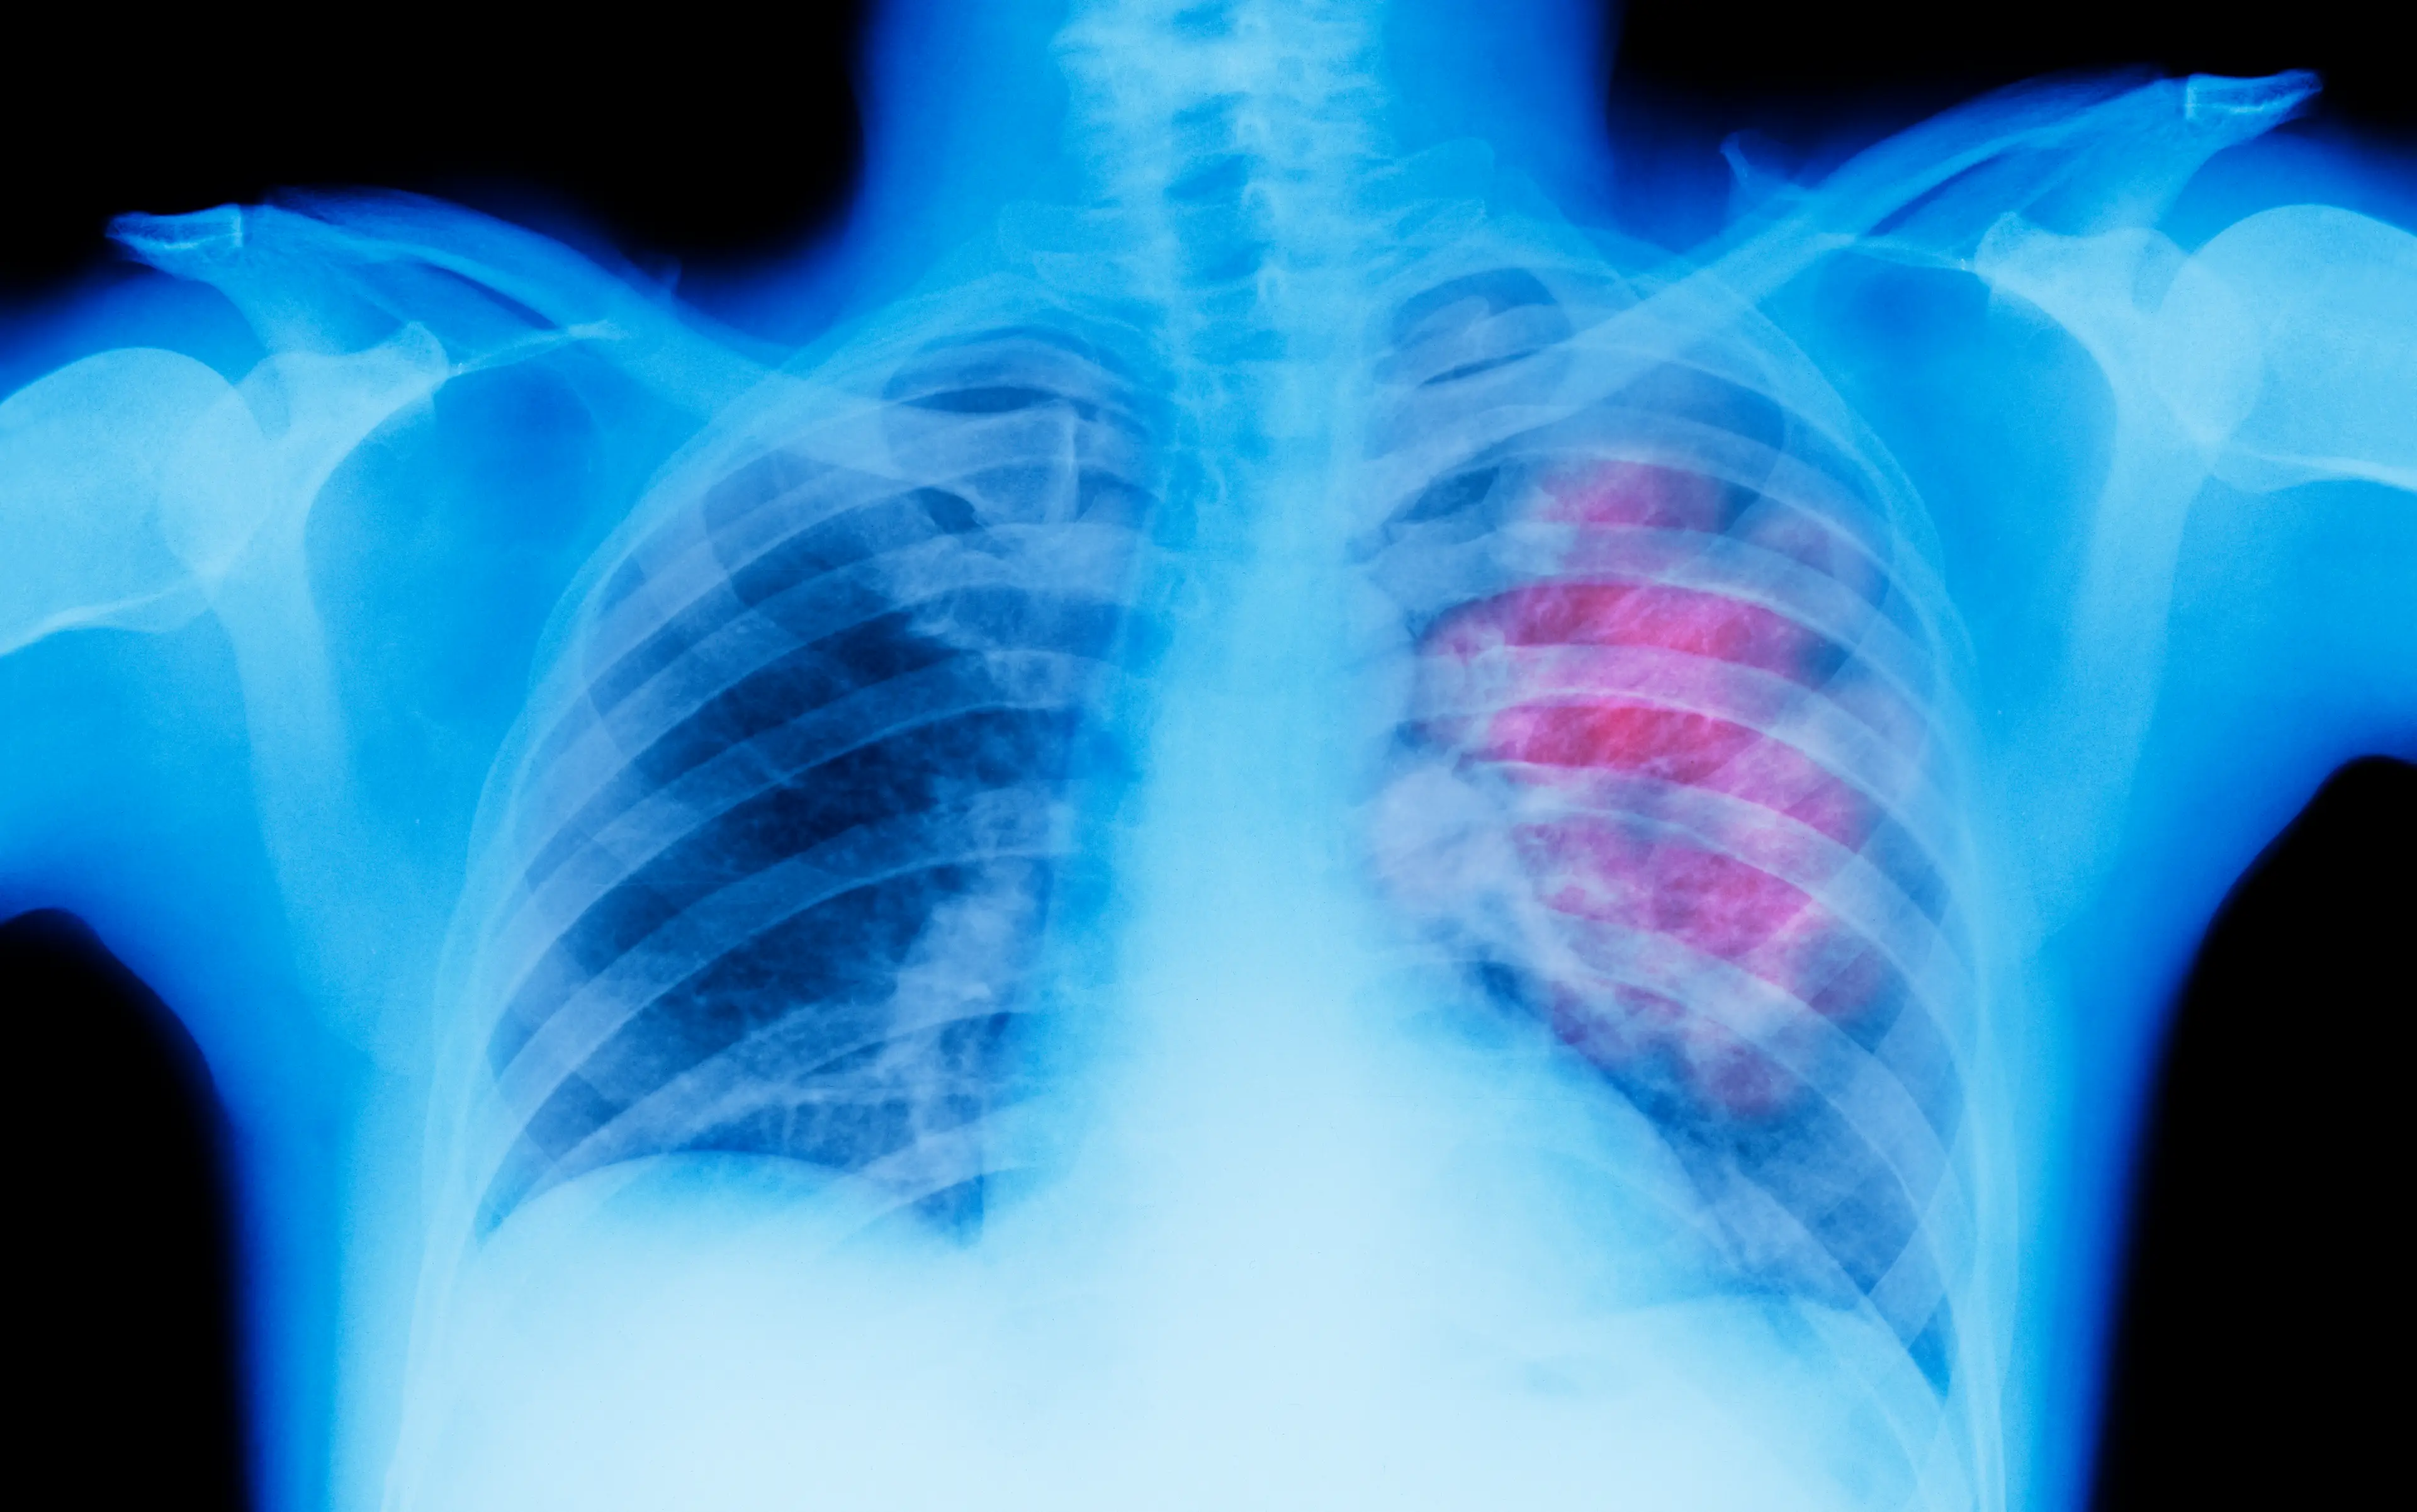

They are calling on regulators to step in to help people quit, following their finding that there is a 'likely' cause of oral and lung cancers.

“On the basis of all of that knowledge … we determined e-cigarettes are likely to cause lung cancer and oral cancer, though we cannot say how great that burden will be,” he said.